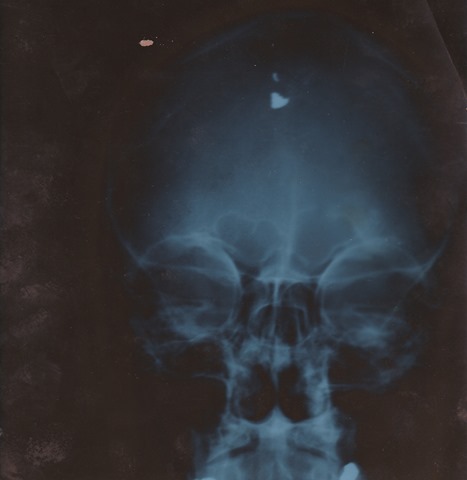

The x-rays of the bullet lodged in the frontal lobe of my brain make the point; life happens to us whether we like it or not. So does death.  So do experiences whose realities are so ruthlessly sudden and savage that when (if) you come out the other side with something resembling your wits about you,  you’ll likely find yourself viewing things from a new perspective.  Kahrmann Head Xray 3

It would be naive to think this kind of behavior is linked solely to for-profit companies. Not so.   I’ve known and know some non-profits run by arrogant, self-absorbed, self-aggrandizing cretins who, in truth, don’t care a wit about the people they say they care about.  Next time you run across a non-profit company in business to help PWD, find out how many PWD they employ. Find out how many PWD are on their board of directors. And, while you’re at it, find out Kahrmann Head Xray 2what they do with the money they raise. See how much is used to directly benefit the lives of those they are said to care about. Find out – to the penny.